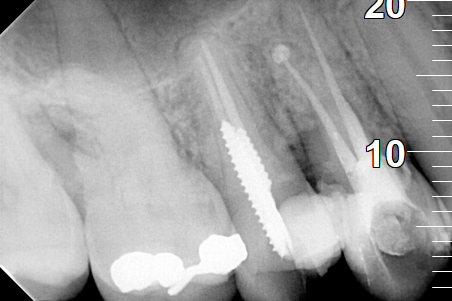

Root canal retreatment

BEFORE

BEFORE